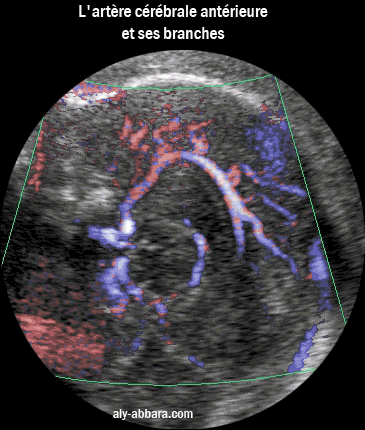

Artère cérébrale antérieure et ses branches

L'artère cérébrale antérieure devenant l'artère péricalleuse et en arrière la veine cérébrale interne